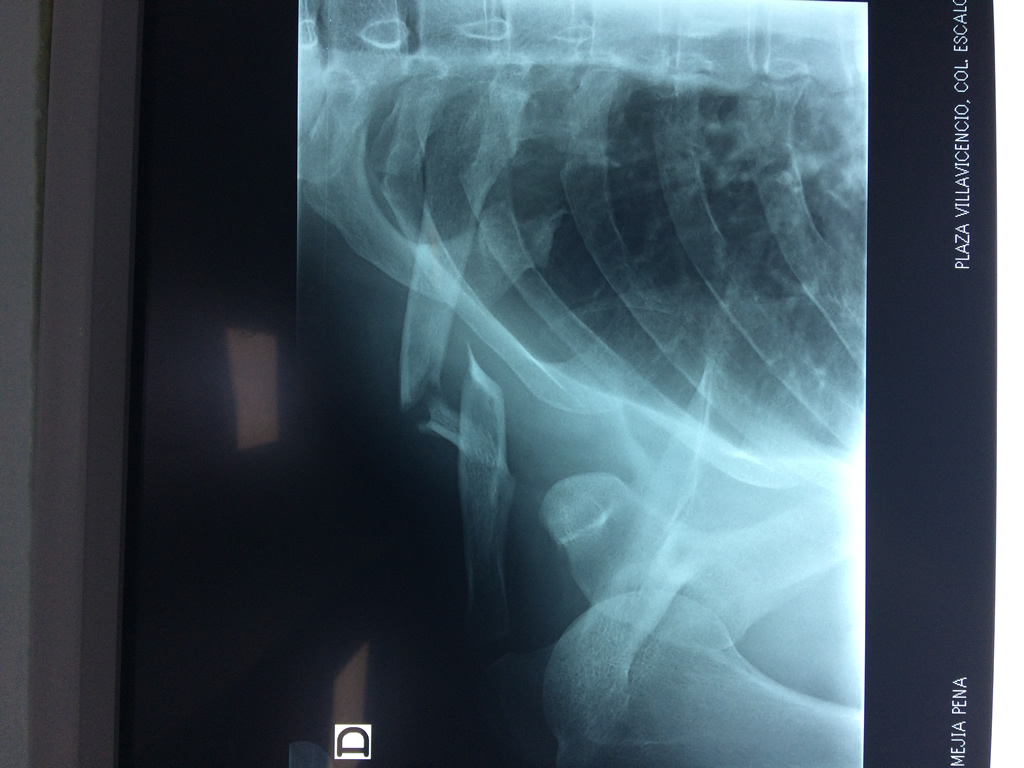

Calcaneo - Clavícula

La clavícula es un hueso largo, con forma de "S" itálica, situado en la parte anterosuperior del tórax. Junto con la escápula forman la cintura escapular. Se puede palpar por toda su longitud y se extiende del esternón al acromion de la escápula, siguiendo una dirección oblicua lateral y posterior.